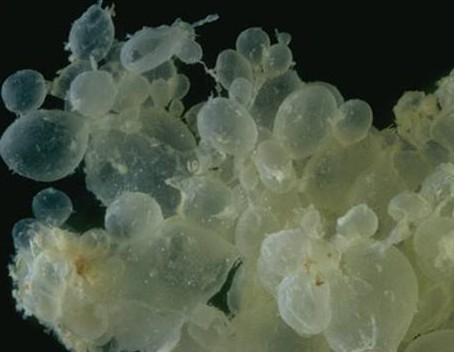

小婷腹部日渐隆起,7月底,小婷怀孕六个多月,突然出血了,量还很大。丈夫吓坏了,赶紧把她送到了东阳市人民医院。检查结果却让人大跌眼镜,B超检查显示,子宫内充满了水泡状的东西,就跟葡萄一样,根本没有胎儿,这就是常说的葡萄胎。

医生解释说,小婷这种情况属于妊娠后胎盘绒毛滋养细胞增生,间质高度水肿,形成大小不一的水泡,水泡间相连成串,形状就像葡萄一样。发病率大约为1/1000。换句话说,就是胎儿没正常发育。

葡萄胎是受孕时受精卵出现的某些异常引起的。子宫内没有正常发育的胎儿,而是有一堆样子有点像葡萄的水泡。葡萄胎分为两类:完全性葡萄胎:胎盘绒毛全部受累,无胎儿及其附属物,宫腔内充满水泡;部分性葡萄胎:仅部分胎盘绒毛发生水泡状变性,宫腔内尚有存活或已死的胚胎。在自然流产的组织中发现40%病人有一定的水泡样变性,但不诊断为葡萄胎。